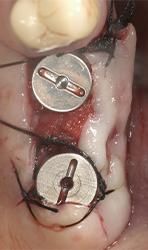

The aim of conservative implant surgery is to create a surgical site for implants by displacing a portion of native residual bone using blades and osteotomes pushed by Magnetic Max (Figs. 5a-5e).

Fig. 5a Fig. 5b

Fig. 5c Fig. 5d

Fig. 5e